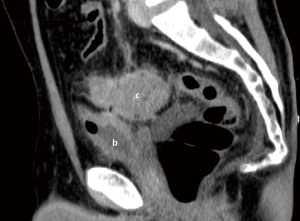

A 55-year-old Caucasian male presented to the emergency room with acute lower abdominal pain and a 1-week history of refractory constipation. He did not report stranguria, pneumaturia, or fecaluria. Past medical history was unremarkable except for multiple recurrent episodes of acute sigmoid diverticulitis. Blood pressure was 130/78 mmHg, heart rate 100 bpm, and oxygen saturation 97% on room air. Body temperature was normal. Physical exam showed mild abdominal distension and tenderness in the lower abdominal quadrants. Abdominal ultrasound showed a small fluid collection in the left lower quadrant. Blood tests showed increased C-reactive protein (13.7 mg/dL) and white blood count (12,500/µL with 86% neutrophils). Plain abdominal X-ray did not reveal free air nor air-fluid images. A CT scan showed a complicated distal left colon diverticulitis with a long segment (7 cm) wall thickening, luminal narrowing (Figure 2A), and multiple perivisceral abscesses (Figure 2B). Moreover, air bubbles inside the bladder were visible (Figure 3), raising the suspicion of a colovesical fistula (Figure 4A,4B). The patient underwent a cystoscopy, which confirmed the presence of a fistula on the posterior-lateral wall of the bladder 2 cm above the vesical trigone (Figure 5). A colonoscopy ruled out the presence of malignancy. The patient was treated with a Foley catheter, clear liquid diet, and broad spectrum antibiotics. Blood tests normalized in a few days, and the patient was discharged home. Readmission for surgical treatment was planned in 3 weeks.